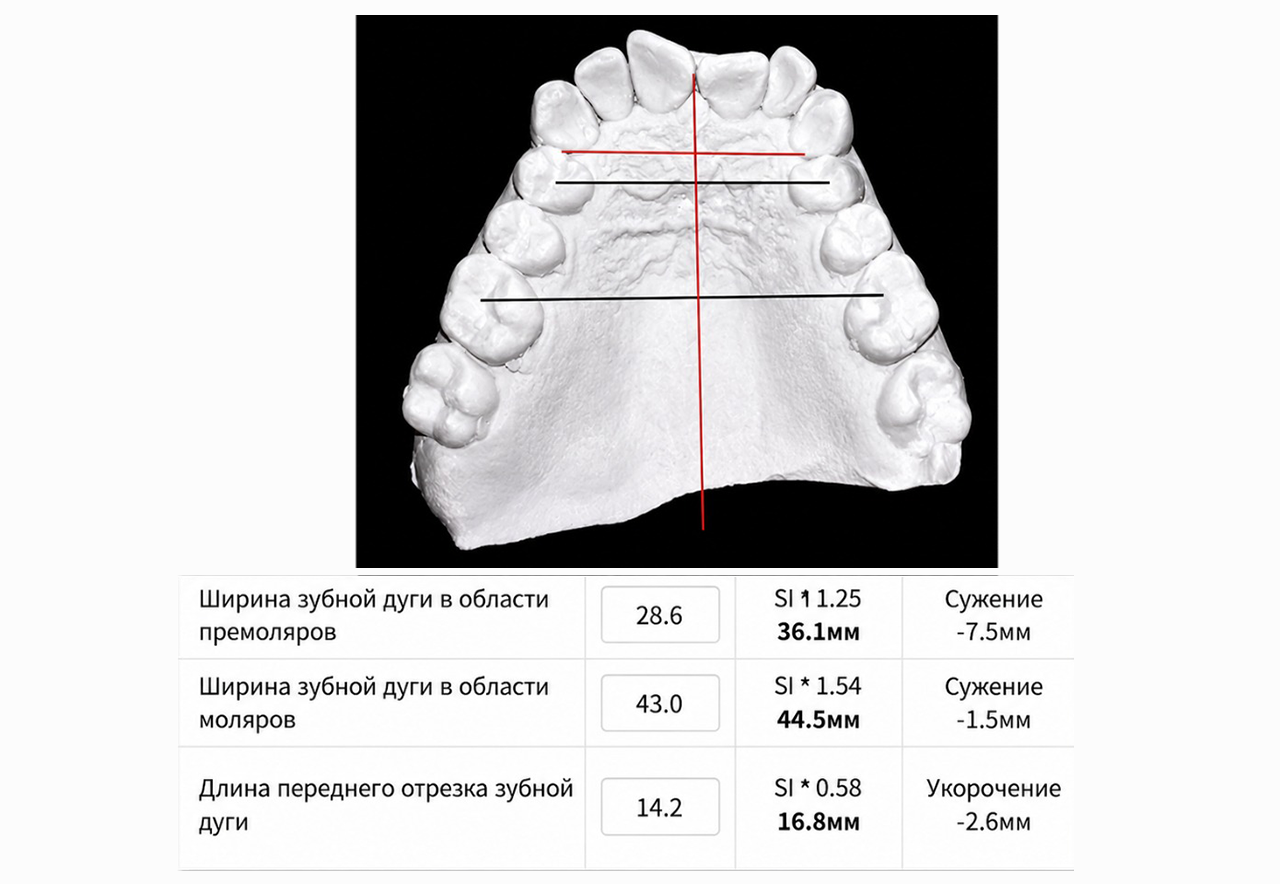

- С помощью специального программного обеспечения с математической точностью производим все рассчеты будущего лечения.

Будут произведены математические рассчеты будущего лечения